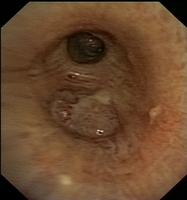

Squamous cell (epidermoid) carcinoma